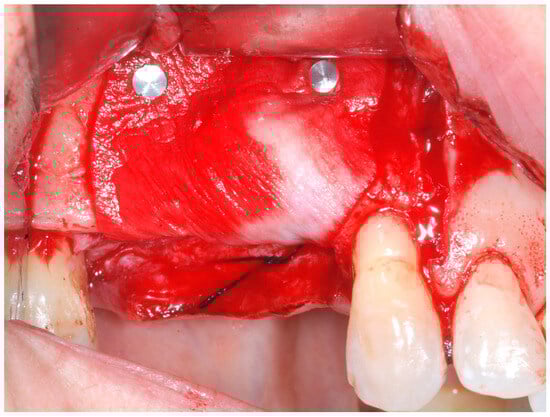

The cortical bone plate was perforated at numerous locations using a round bur in order to allow access of the cells from the bone and bone marrow to the area of regeneration. Subsequently, granules of cancellous deproteinized bovine bone mineral (DBBM) (Bio-Oss, Geistlich AG, Wolhusen, Switzerland), were placed in the defect area (Figure 5). A collagenous resorbable membrane (T-Gen, HYUNDAI BIOLAND Co., Ltd., 162, Gwahaksaneop 3-ro, Ochang-eup, Cheongwon-gu, Cheongju-si, Chungcheongbuk-do, 28125, Republic of Korea) was shaped and trimmed to cover the graft and to extend 2–3 mm onto the intact bony borders of the defect. The membrane was hydrated and the fixation was accomplished using fixation pins (MC Bio S.r.l., Como, Italy) (Figure 6).

Figure 5. DBBM graft to cover the defect area.